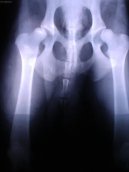

Ortopedie - DKK :

Ortopedie - DKK

Zobrazeno: 1086x